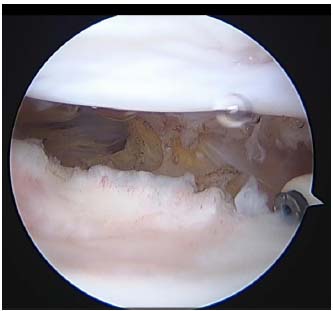

All the patients were placed in the supine position on an operating table. A tourniquet was applied to the thigh with the knee in the maximum possible flexion position to minimize capture of the quadriceps femoris muscle. The procedure was performed using the three-portal technique with two standard anterolateral and anteromedial portals in addition to the accessory superolateral portal [8, 9]. Tissue adhesions were identified (Fig. 1) and debrided using a radiofrequency device (Arthrocare, Arthrocare Sports Medicine, USA) (Fig. 2). Subsequently, gentle manipulation was performed by applying slight pressure on the tibial tubercle to avoid fractures or disruption of the extensor mechanism. After the operation, continuous passive motion was immediately initiated.

Arthroscopic view from an anterolateral portal.

Tissue adhesions were identified.